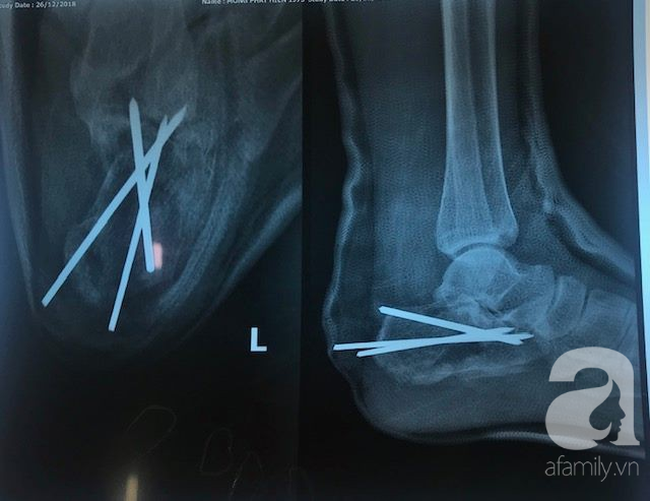

Phần cẳng chân: gãy xương chày chân trái; phần gót chân gãy rất nặng và phức tạp mất hết các mốc giải phẫu của cổ chân.

Bằng sự quyết tâm, 3 ê kíp mổ khác nhau đã hợp sức liên tục trong gần 5 giờ. Bệnh nhân được phẫu thuật giải ép, hàn liên đốt sống, phẫu thuật kết hợp xương đùi, xương gót, bó bột cẳng chân và nắn chỉnh các xương gãy.